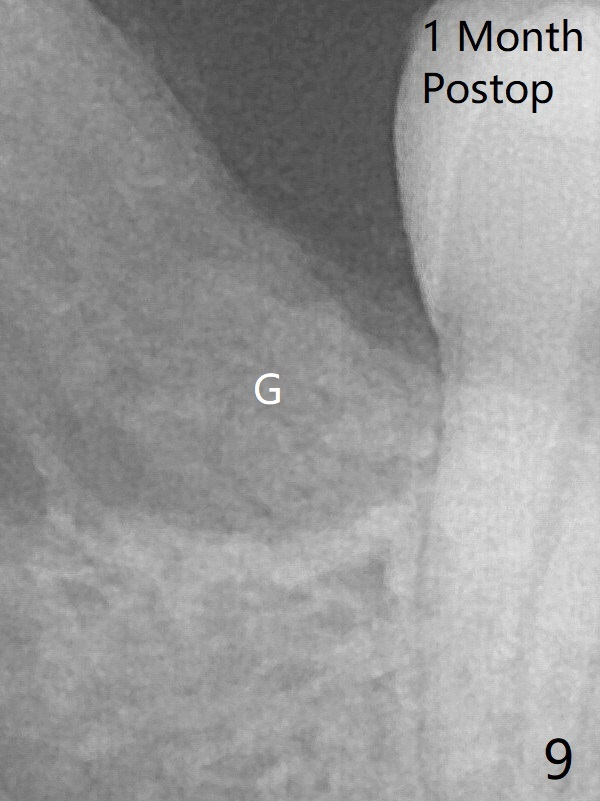

The transverse cortex connecting to the lamina dura (Fig.5 *) is obliterated when allograft is placed (Fig.7 G). The part of the graft remains in place 1 month postop (Fig.9) in spite of wound dehiscence (Fig.8). The bone graft loss is indicated by the fact of the reappearance of the transverse cortex (Fig.9).